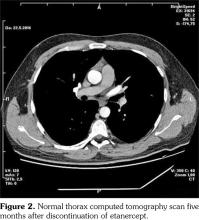

A 29-year-old male patient who had AS for 13 years applied to our rheumatology outpatient clinic for routine yearly control. His AS had been under control with etanercept for 43 months. After the routine follow-up evaluation, a thorax computed tomography scan was performed because of hilar enlargement in the chest X-ray. Multiple lymphadenopathies, the largest one with 2 cm in diameter, were detected in computed tomography scan (Figure 1).

Lymph node biopsy was performed by broncoscopy and endobronchial ultrasonography. Biopsy result was compatible with granulomatous disease. All the infectious studies performed on pulmonary lymph node tissues were negative. Angiotensin converting enzyme level was at the upper limit with a value of 47.6 U/L (normal: 8-52 U/L). Sarcoidosis was found to be compatible with the condition after excluding tuberculosis. Etanercept was ceased following the diagnosis of sarcoidosis. No additional medical treatment was suggested for sarcoidosis. Non- steroid anti-inflammatory drugs were prescribed for the control of AS. Five months later, follow- up thorax computed tomography scan showed resolution of the mediastinal lymphadenopathies (Figure 2).